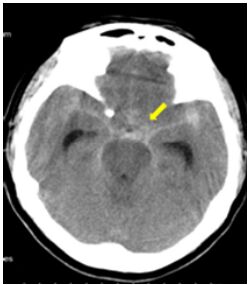

45.下圖箭號所指出血位置為何?

(A)硬膜下腔出血 (B)硬膜外腔出血 (C)蛛網膜下腔出血 (D)腦室出血

46.承上題,下列何者非適當的進一步檢查? (A)CT angiography (B)MR angiography (C)catheter angiography (D)RBC scan for bleeding point